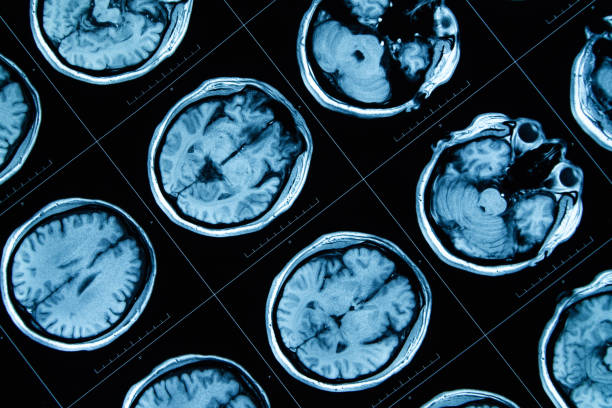

一些臨床試驗表明,MSC治療可提高存活率、減少病理、挽救認知功能衰退、改善疾病癥狀并減少復發。正在進行臨床試驗的常見神經退行性疾病包括阿爾茨海默病、肌萎縮側索硬化癥 (ALS)、多系統萎縮 (MSA)、帕金森病 (PD) 和脊髓損傷 (SCI)。

06、間充質干細胞治療阿爾茨海默病

阿爾茨海默病會導致癡呆,其特征是患者語言、記憶、認知能力和解決問題的能力下降。這會擾亂患者的生活方式,久而久之會致命。這種疾病是由大腦特定部位的神經細胞受損或破壞引起的。

考慮到再生醫學方法治療阿爾茨海默病,MSC被認為是有前途的細胞治療候選藥物,因為它們具有阻止疾病進展和再生受損神經組織的能力。

有證據表明,UCB-MSC可防止β-淀粉樣肽 (Aβ) 斑塊沉積并激活小膠質細胞。MSC還能誘導內源性神經發生,從而保留或恢復阿爾茨海默病患者的認知功能。